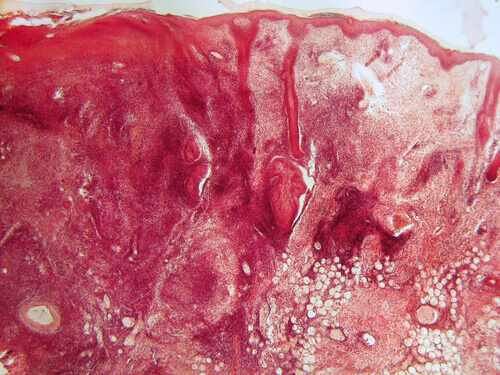

Пошкодження шкіри: приблизно 80% хворих на системний червоний вовчак страждають на надмірну чутливість до сонячних променів. Є три види пошкодження шкіри при цьому захворюванні, а саме:

- Гострий шкірний вовчак (50% випадків): найпоширеніший різновид цього аутоімунного захворювання. Його основною характеристикою є еритема обличчя (почервоніння) у вигляді крилець метелика. Слідів та шрамів цей симптом не залишає, і виникає він лише після тривалого перебування на сонці. Іноді гострий вовчак може супроводжуватися появою висипань червоного кольору на інших частинах тіла (плечі, шия та руки).

- Дискоїдний шкірний вовчак (10-20% випадків): після тривалого перебування на сонці у хворого на вовчак можуть з’явитися симетричні пухирчаті утворення на плечах та шиї. Шрамів вони не залишають, проте шкіра може втратити свій природний колір.

- Хронічний шкірний вовчак (30% випадків): у хворих на цей різновид вовчака з’являються виразкоподібні пошкодження слизової оболонки носової та ротової порожнин.